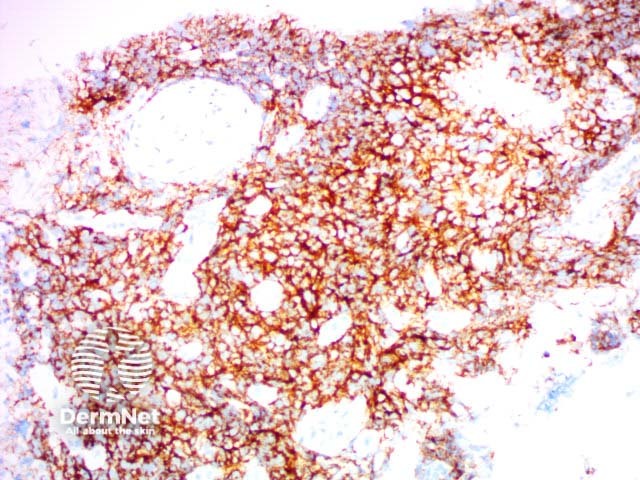

Can be used in the diagnosis of Hodgkin lymphoma and anaplastic lymphomas. Large cells: Golgi apparatus and membranous staining |

CD30